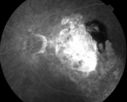

Disciform Scar

87 year old male seen for neovascular macular degeneration. Patient had huge disciform scar and lipid.